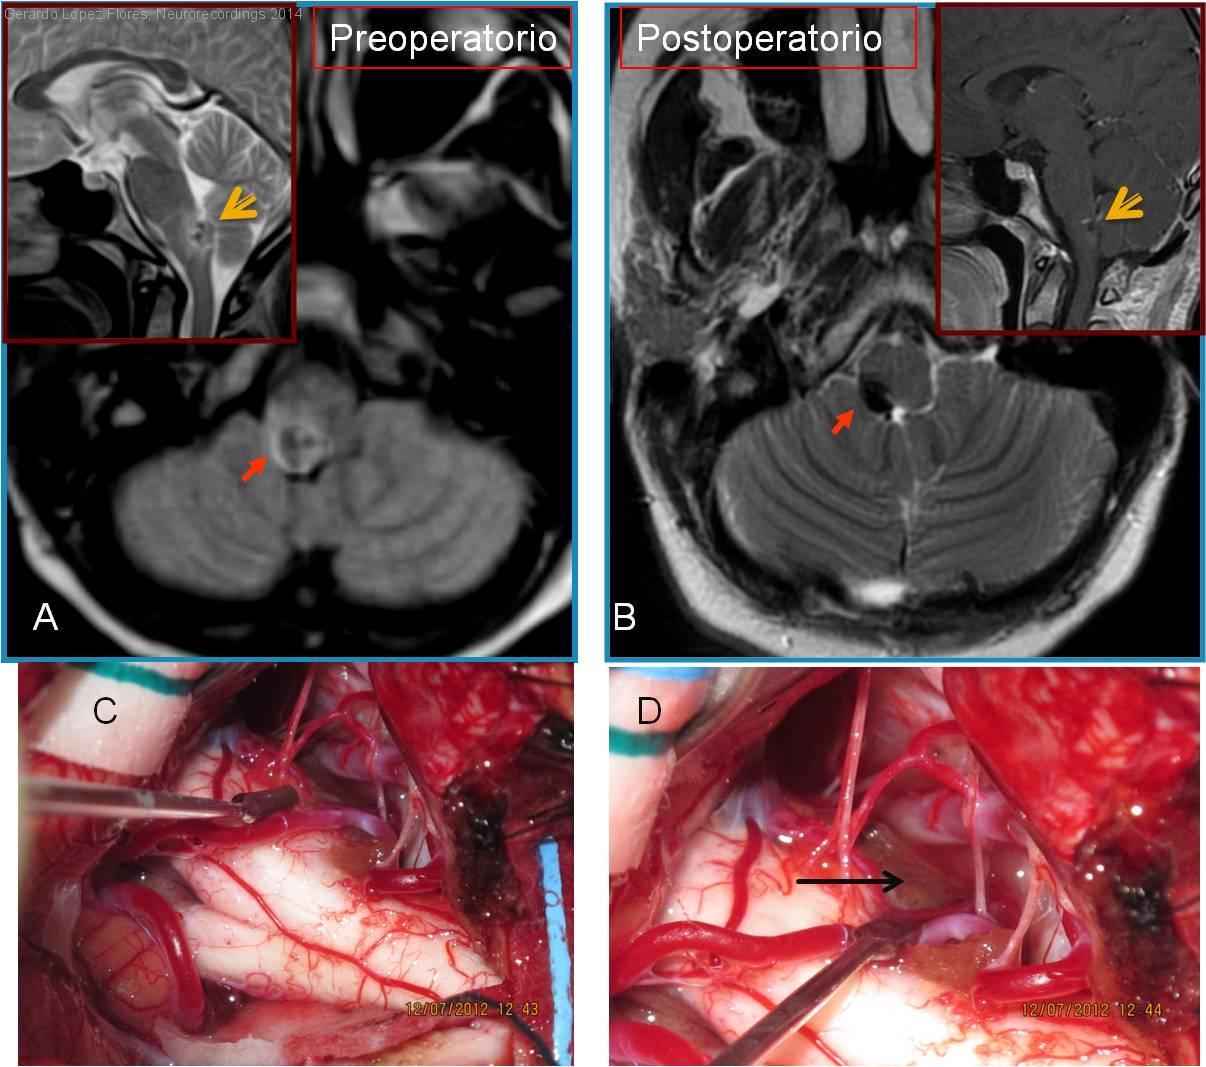

Malformacion Cavernosa del bulbo raquideo

Mujer | 19 años

Diagnóstico final: Angioma cavernoso. Cavernoma